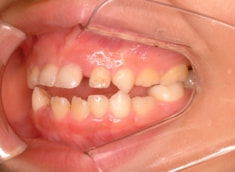

治療前

治療開始時